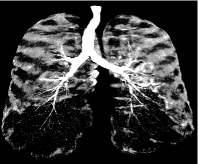

Refer to caption

Figure 4: Maximum intensity projection view of the probability image obtained from the voxel-classifier. Brighter regions correspond to higher probability, and hence more likely to belong to airways.

All CT images were pre-processed and converted into probability images using a kNN-based voxel classifier trained to distinguish airway voxels from background 23. Thus obtained probability images have probability close to 111 in regions that are classified to be inside the airways and close to 0 outside. These images match the profile function described in Section II.A., wherein, the structure of interest is bright (high probability) in a dark background. An example probability image is shown in Figure 4. Noise in the image is due to several factors including acquisition, interfering vessels, ribs and lung tissue.